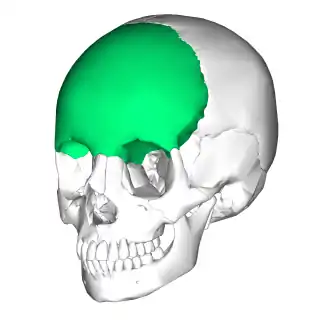

Hueso frontal

El hueso frontal ([TA]: os frontale) es un hueso del cráneo. En el ser humano es impar, central, simétrico y plano, con dos caras (endocraneal y exocraneal) y un borde circunferencial.

- Situación

El hueso frontal se encuentra en la parte anterosuperior del cráneo por delante de los huesos parietales y un poco por arriba del esfenoides, y montado sobre el etmoides, y el macizo facial. El hueso frontal ocupa la superficie de la cara que se corresponde con la frente y la prominencia cubierta por las cejas.

El hueso frontal presenta dos porciones:

- una porción vertical y superior, regularmente convexa que suele recibir el nombre de escama frontal y forma parte de la bóveda craneal; y

- una porción horizontal e inferior, que constituye parte de la base del cráneo (piso etmoido-frontal), parte del techo de las órbitas y parte de los senos etmoidofrontales (cavidades pneumáticas paranasales).

Visto en conjunto, el hueso frontal presenta dos caras y un borde. Una cara es posterior y cóncava: la cara endocraneal o cerebral; la otra cara es anterior, convexa hacia adelante: es la superficie exocraneal o cara cutánea. Ambas caras están separadas por un borde circunferencial o borde supraorbital.